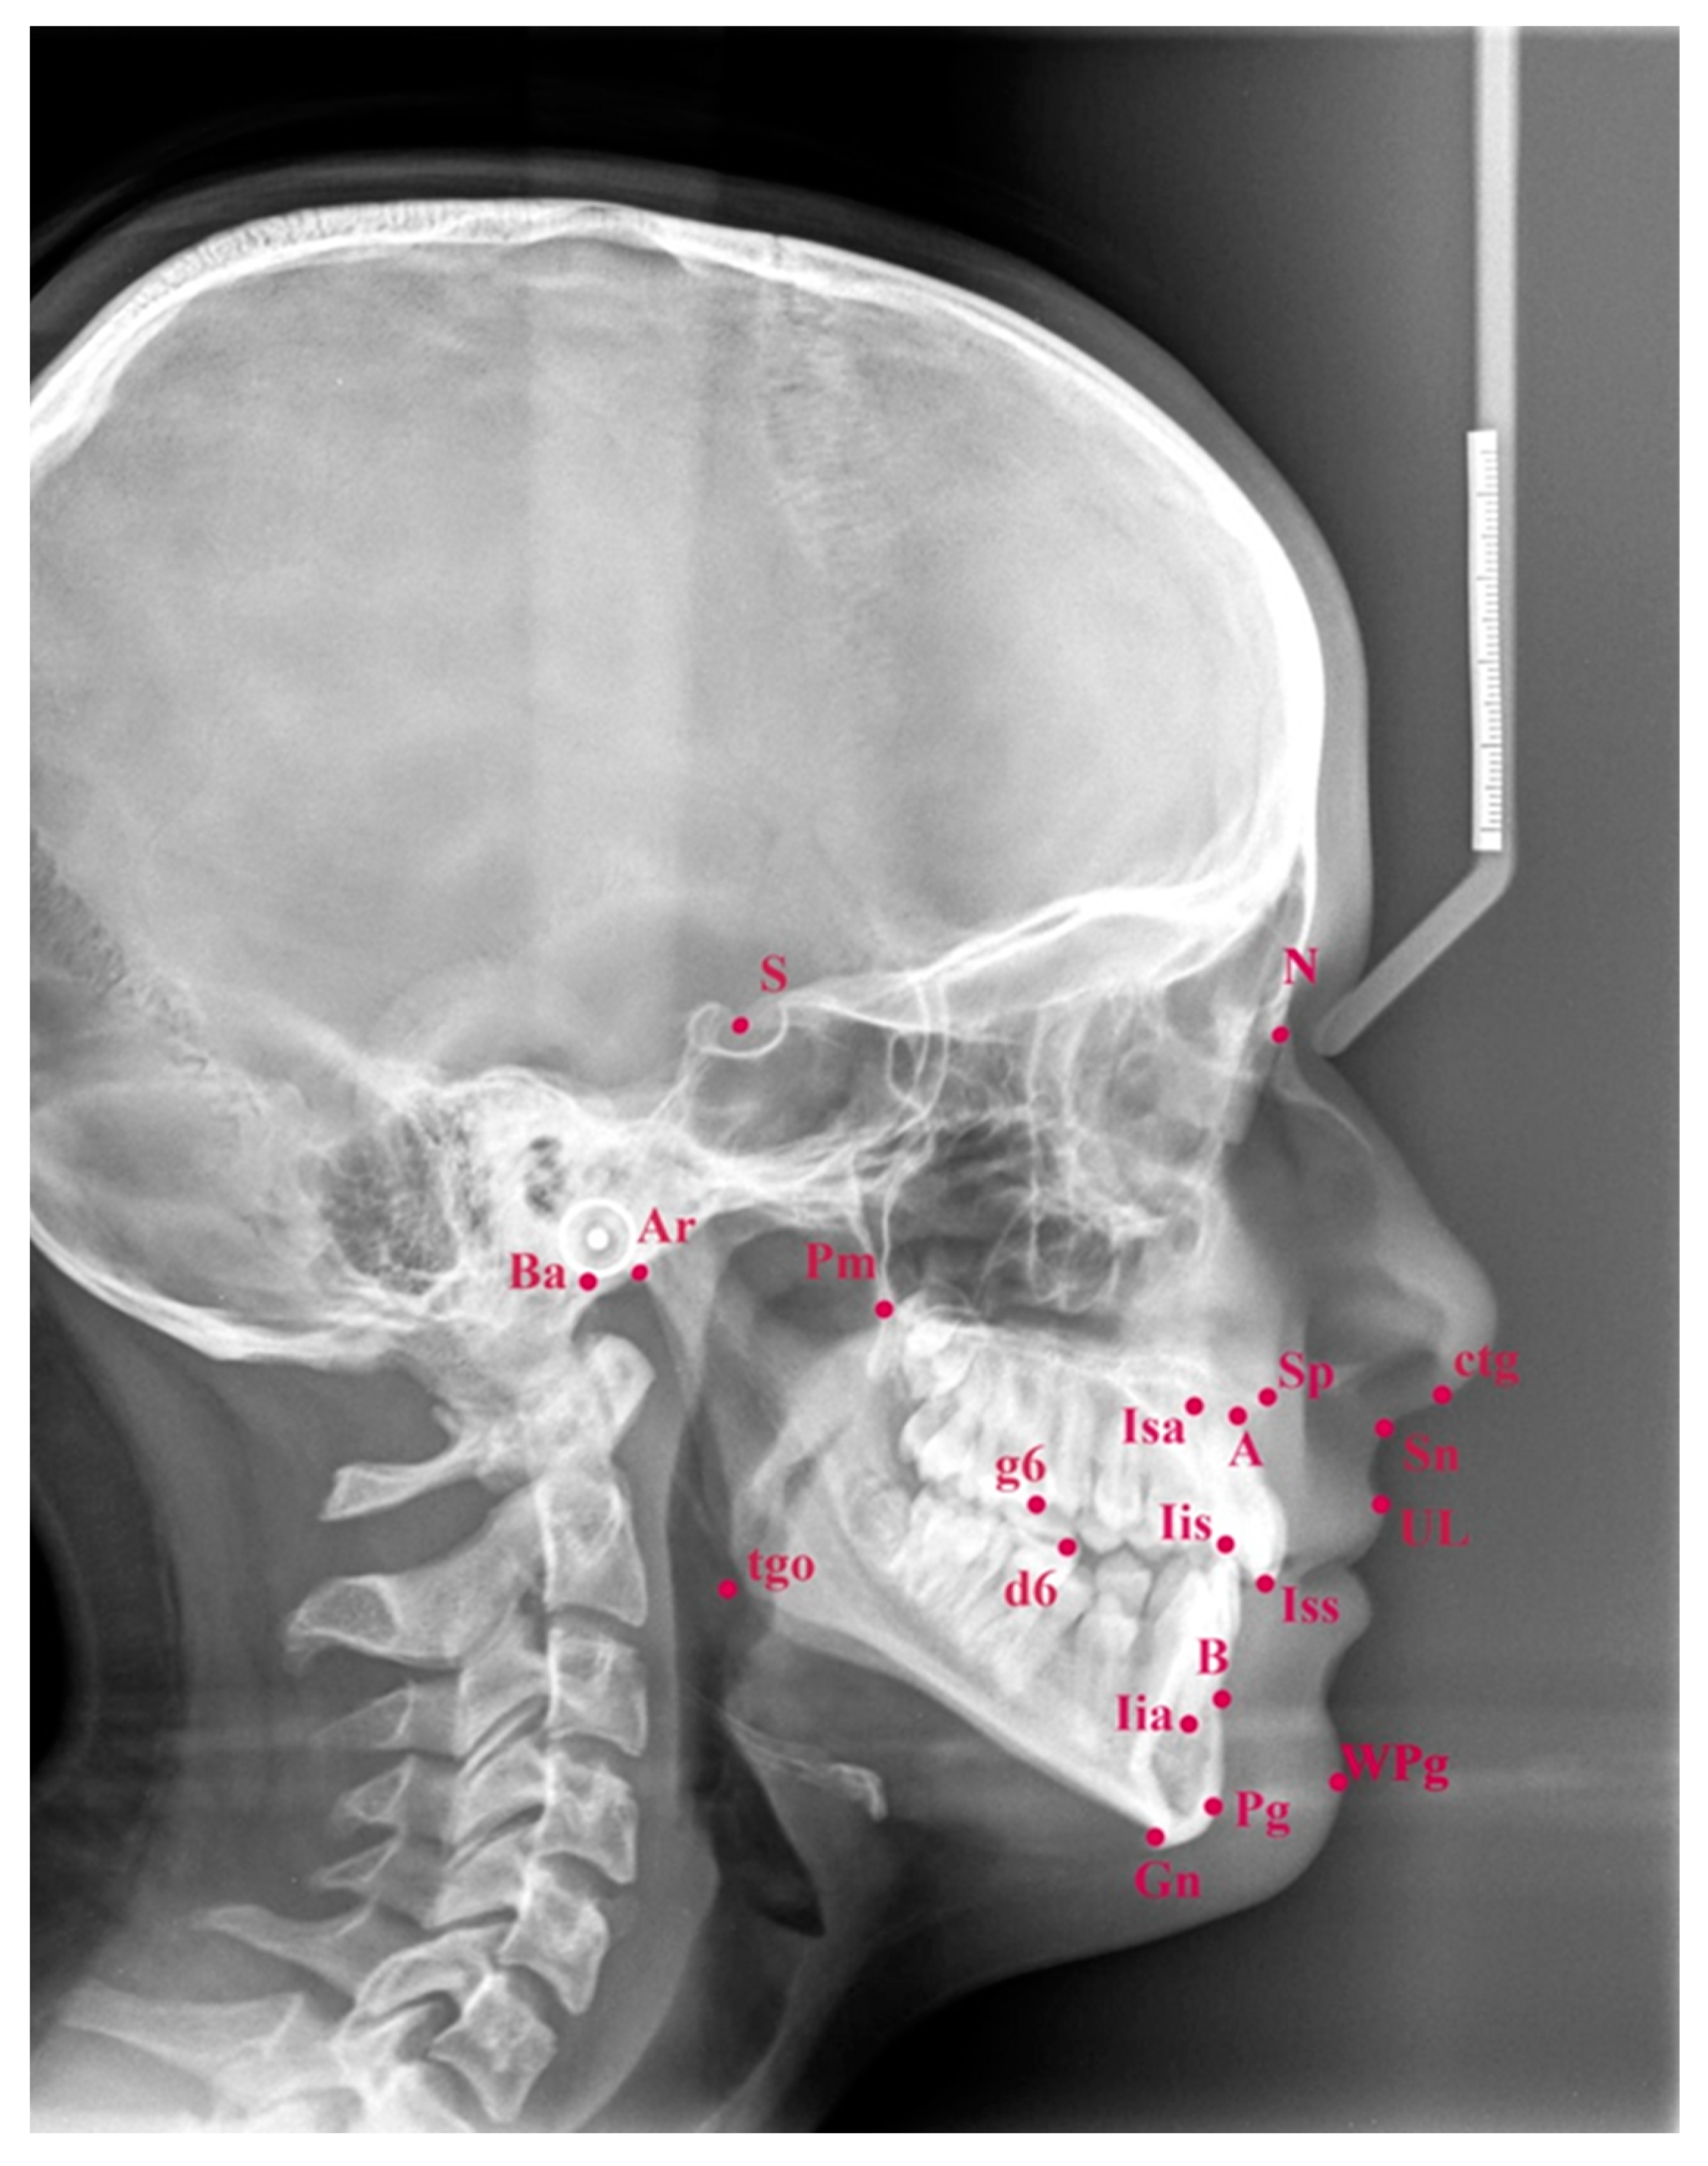

| Abbreviation | Mean Value | Range | Reference Points or Lines |

|---|---|---|---|

| SNA | 82 | 79–85 | Sella-Nasion-A: Sagittal maxillary position referring to cranial base |

| SNB | 80 | 77–83 | Sella-Nasion-B: Sagittal position of the mandibular alveolar part referring to cranial base |

| ANB | 2 | 0–4 | A-Nasion-B: Sagittal relation between the maxilla and mandible |

| SNPg | 82 | 78–84 | A-Nasion-Pg: Sagittal position of the chin referring to cranial base |

| NL-NSL | 8 | 4–12 | Maxillary base-cranial base: Vertical maxillary inclination relative to cranial base |

| ML-NSL | 28 | 23–33 | Mandibular base-cranial base: Vertical mandibular inclination relative to cranial base |

| ML-NL | 20 | 12–27 | Maxillary base-cranial base: Vertical jaw relationship |

| NS-Ba | 132 | 128–136 | Inclination of the clivus to cranial base |

| Gn-tgo-Ar | 122 | 115–129 | Gonial angle |

| H | 9 | 6–12 | Upper lip–soft-tissue chin–NB line: Angle between the line of the upper lip and soft-tissue chin relative to line NB—inclination of the soft tissue profile |

| 1+:1− | 133 | 125–141 | Angle between the long axes of upper and lower central incisors |

| 1+:NA | 21 | 18–25 | Upper incisor inclination to NA line |

| 1+:NB | 24 | 20–28 | Lower incisor inclination to NB line |

| Nasolabial angle | 110 | 103–117 | Nasal base–upper lip: Angle between nasal base and upper lip |

| Index | 80 | 73–87 | Proportion between the upper and lower face height (in percentage) |

| Pg:NB (mm) | 2.3 | 0.3–4.3 | Distance Pg–NB line: Describes chin prominence |

| 1+:NA (mm) | 3.7 | 1.7–5.7 | Distance: Incisal edge of the upper central incisor–NA line |

| 1−:NB (mm) | 3.8 | −1.2–8.8 | Distance: Incisal edge of the lower central incisor–NB line |

| Wits (mm) | 0 | −2–2 | Distance: Perpendicular projections of points A and B on the occlusal plane |